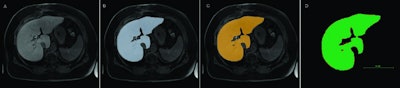

Many of these 3D analyses require segmentation of the organs. Organs are subdivided into individual anatomical or functional sections to provide the requesting physician with the desired information. This segmentation takes a lot of time if the radiologist has to manually do it. However, CT software programs are now available, which can at least partially automate segmentation.

The segmentation is completed within a minute. The validation consequently shows that the trained algorithm can manage the segmentation of the liver with high accuracy using the MRI dataset.

"In theory, a person can segment 100% accurately, but, due to the time-consuming nature of the activity, this is only possible to a limited extent in routine clinical work," Verloh added. The algorithm, on the other hand, is very fast: In an MRI scan with 64 layers, the neural network requires an average of 60 seconds for segmentation.